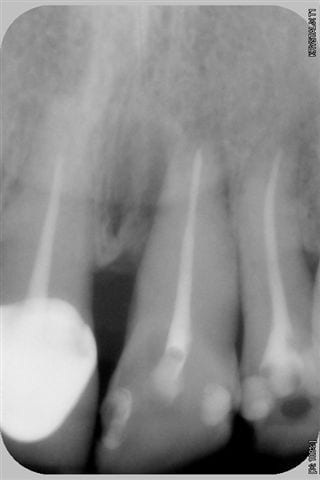

voici un cas traité en dentisterie globale à l'aide du laser en paro et du cerec en occluso, le cas à été terminé en 2010, cette semaine examen microbiologique de routine avec maintenance paro, il n'y a plus de flore pathologique dans la bouche de cette patiente

Emma

salut ceramik, toujours aussi contente de te lire, tes désirs sont des ordres, radios faites en 2010, les photos dates de juin 2010, les papilles entre 11 et 21 sont entrain de se reconstruire petit à petit, au prochain contrôle de maintenance, je ferai des radios et des photos pour montrer l'évolution engendrée par la biostimulation laser diode.

Joli cas Emma, juste une remarque, le travail de l'espace inter incisif en jouant sur la convexité des profils d'émergence masquerait le manque immédiat de papille et à terme la papille se reconstruirait plus rapidement.

Il est vrai qu'au vu de la difficulté initiale du cas ce type de détail peut passer à la trappe.

très belle reconstruction par cfao directe!!!!!